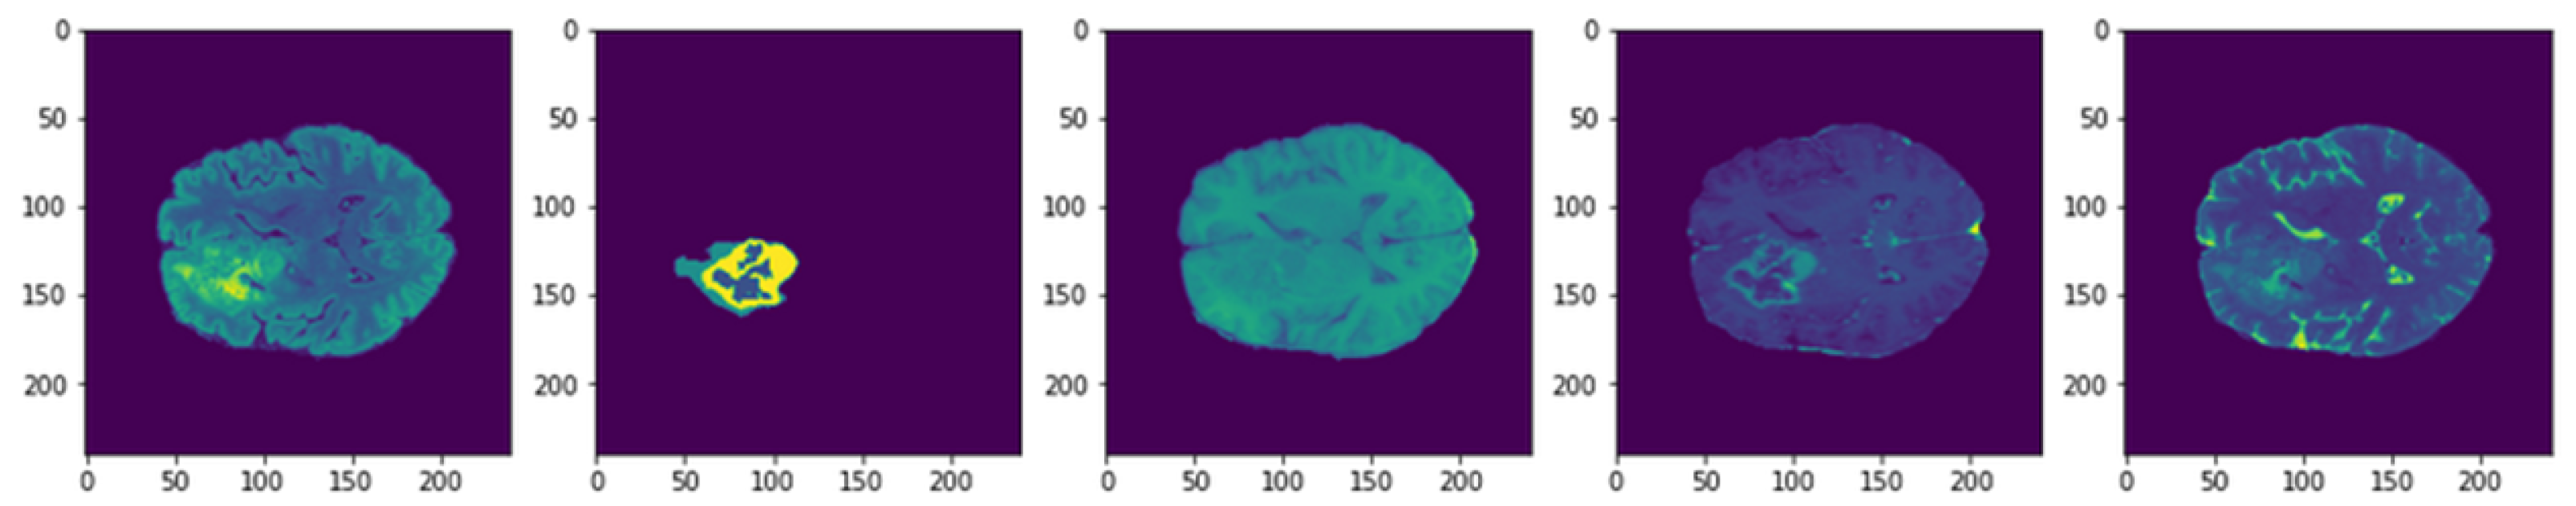

4.1. Dataset Description

4.4. 3D U-Net Segmentation Model